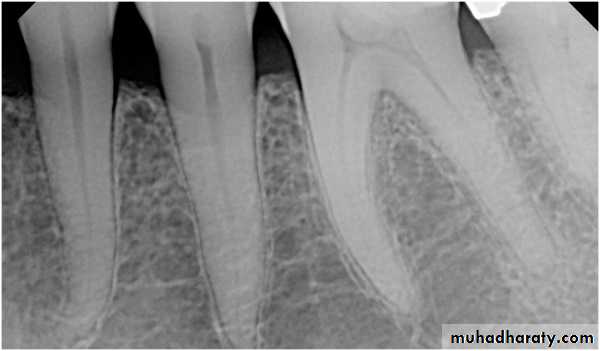

Luxation of teeth as a result of trauma may result in calcific metamorphosis, a condition that can, in a matter of

months or years, lead to partial or complete radiographic obliteration of the pulp chamber. The cause of radiographic obliteration is excessive deposition of mineralized tissue resembling cementum or, occasionally, bone on the dentin walls, also referred to as internal ankylosis

Clinically, the crowns of teeth affected by calcific metamorphosis may show a yellowish hue compared with adjacent normal teeth.